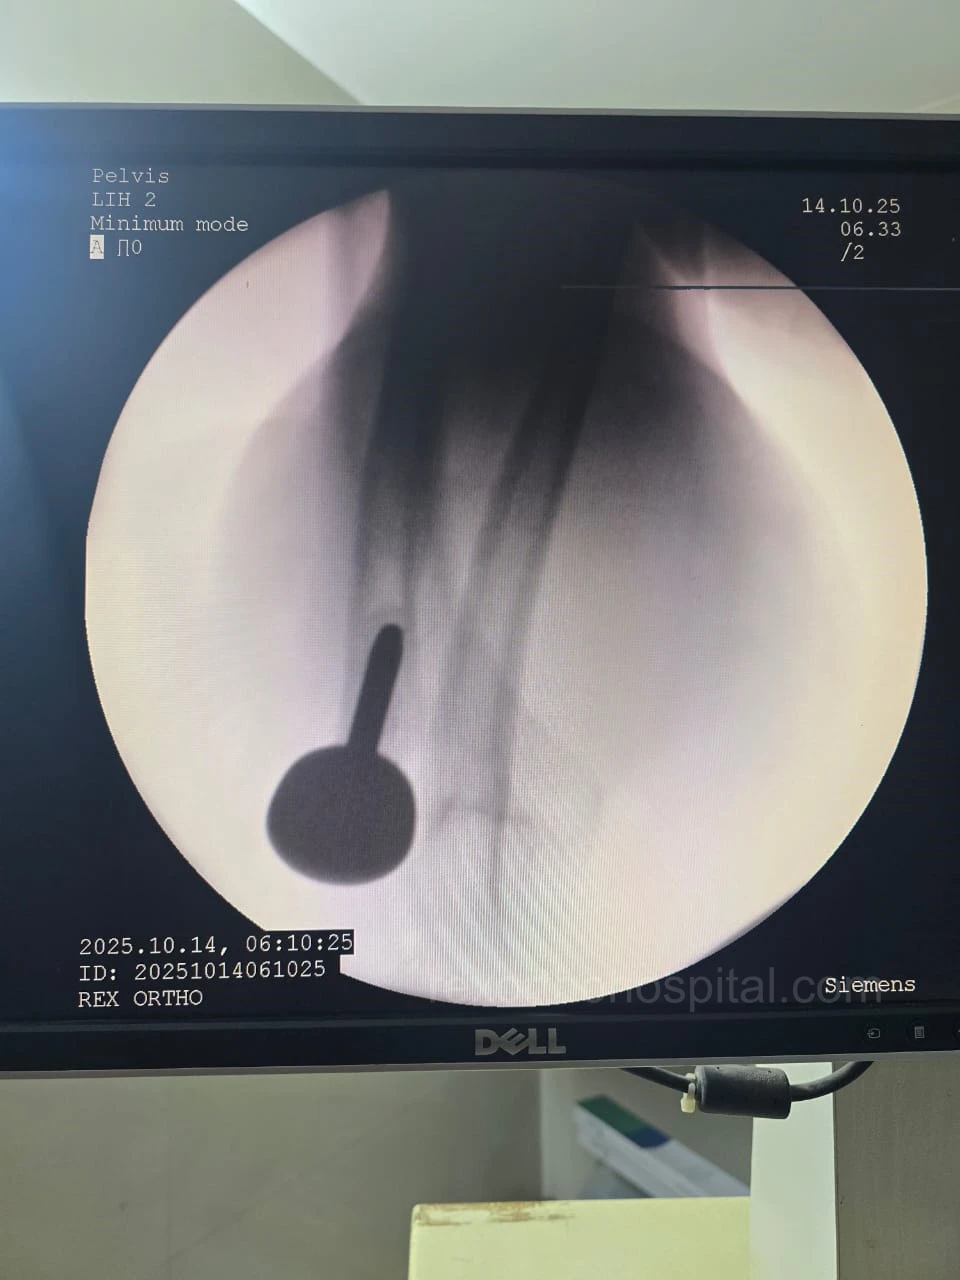

Elbow stiffness treatment aims to restore smooth movement and reduce pain caused by injury, arthritis, or long-term immobility. Our approach improves flexibility and helps regain everyday function.

From diagnosis to surgery and recovery, our team ensures you receive expert treatment and individual attention throughout your treatment journey